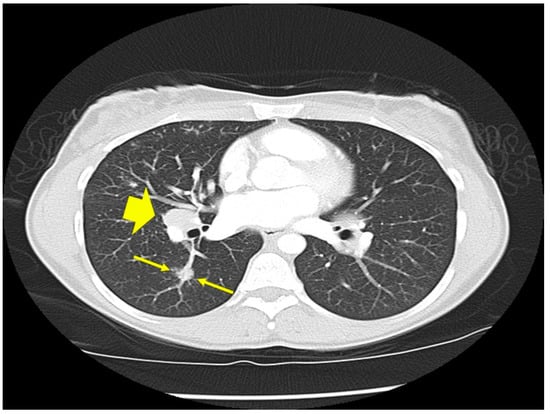

Figure 2.

Chest CT scan image of a patient with pulmonary sarcoidosis, demonstrating lung opacities from granulomatous inflammation around airways (arrows).